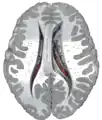

Transverse Cut of Brain (Horizontal Section), basal ganglia is blue | |

Together with the putamen, the caudate forms the dorsal striatum, which is considered a single functional structure; anatomically, it is separated by a large white matter tract, the internal capsule, so it is sometimes also referred to as two structures: the medial dorsal striatum (the caudate) and the lateral dorsal striatum (the putamen). In this vein, the two are functionally distinct not as a result of structural differences, but merely due to the topographical distribution of function.

The caudate nuclei are located near the center of the brain, sitting astride the thalamus. There is a caudate nucleus within each hemisphere of the brain. Individually, they resemble a C-shape structure with a wider "head" (caput in Latin) at the front, tapering to a "body" (corpus) and a "tail" (cauda). Sometimes a part of the caudate nucleus is referred to as the "knee" (genu).[7] The caudate head receives its blood supply from the lenticulostriate artery while the tail of the caudate receives its blood supply from the anterior choroidal artery.[8]